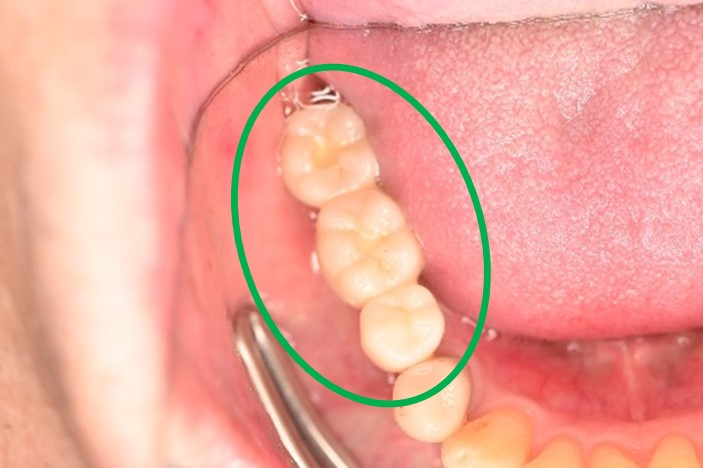

Before

※赤丸を抜歯しました。

After